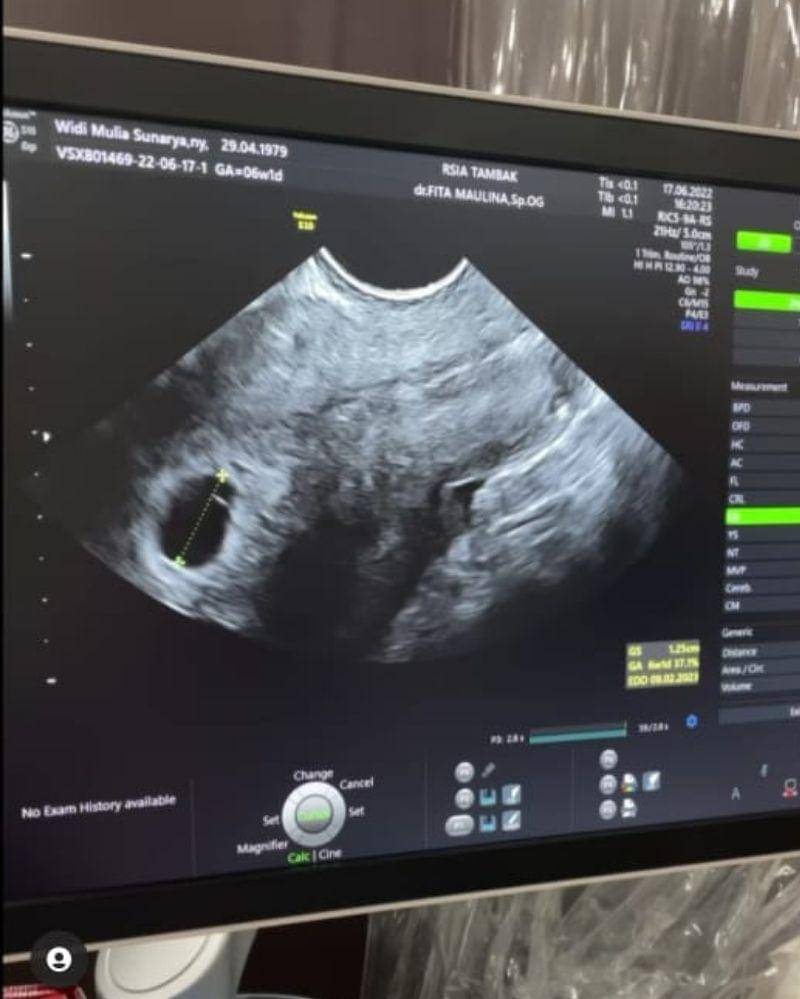

Selanjutnya, dalam video yang ia unggah, Widi terlihat sedang melakukan pemeriksaan ultrasonografi tanpa ditemani suaminya, Dwi Sasono.

"Ya Allah udah enam minggu aja lo, Alhamdulillah," ungkap dokter Fita Maulana, Sp.OG.

Dokter Fita juga menjelaskan mengenai kondisi Widi yang sehat dan tidak ditemukan gangguan apapun.

"Sah ya! Alhamdulilah," ujar dokter Fita lagi. Dengan demikian perempuan kelahiran 29 April 1979 ini akan menjalani kehamilannya tepat di usia 43 tahun.

Kala itu, Widi diketahui melakukan pemeriksaan kehamilannya pada tanggal 17 Juni 2022 Rumah Sakit Ibu dan Anak Tambak, Jakarta Pusat.